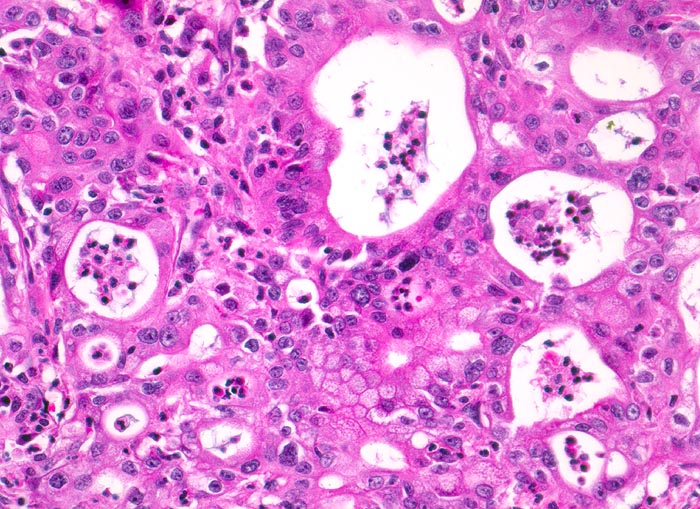

duktales Adenokarzinom des Pankreas

Maligne Tumordrüsen liegen dos à dos und bilden ein kribriformes (siebartiges) Muster. Die Zellkerne sind polymorph, das Chromatin ist vergröbert. Die Lumina der Tumordrüsen sind angefüllt mit neutrophilen Granulozyten.

Unscharf begrenzter weisser derber Herd im Pankreaskopfbereich. Stenosierung und praestenotische Dilatation von Ductus choledochus und Pankreasgang vor der Papille.

Zunehmender schmerzloser Ikterus. Sonographische Darstellung einer 4cm grossen echoarmen Raumforderung im Pankreaskopfbereich. Dilatation des Pankreasganges und des Ductus choledochus. Whipple Operation.

200